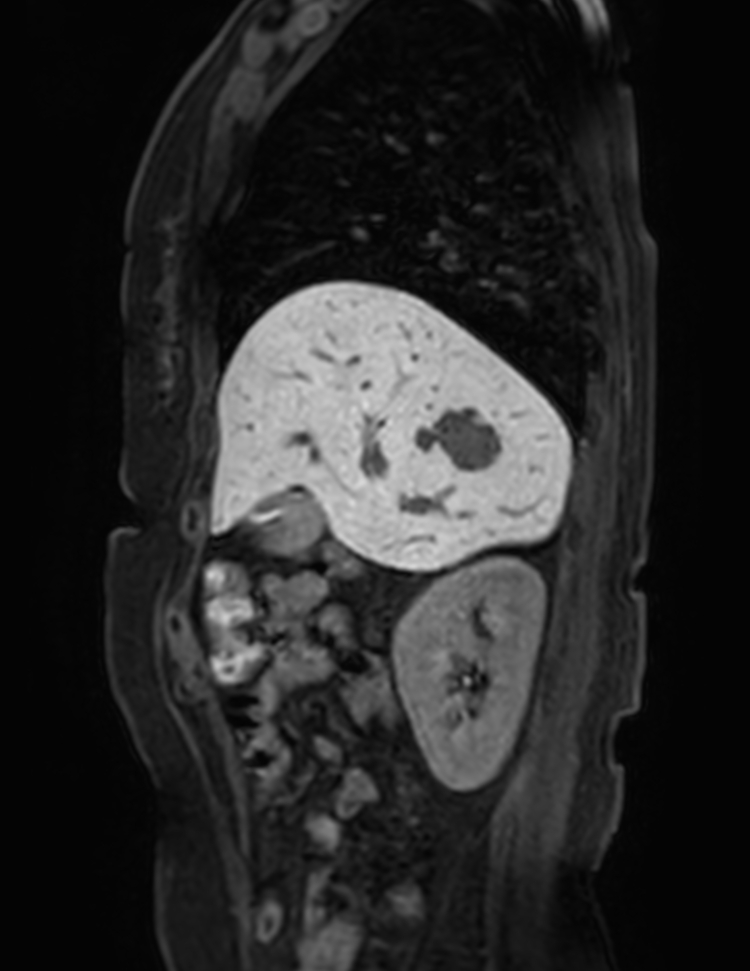

Sagittal eTHRIVE